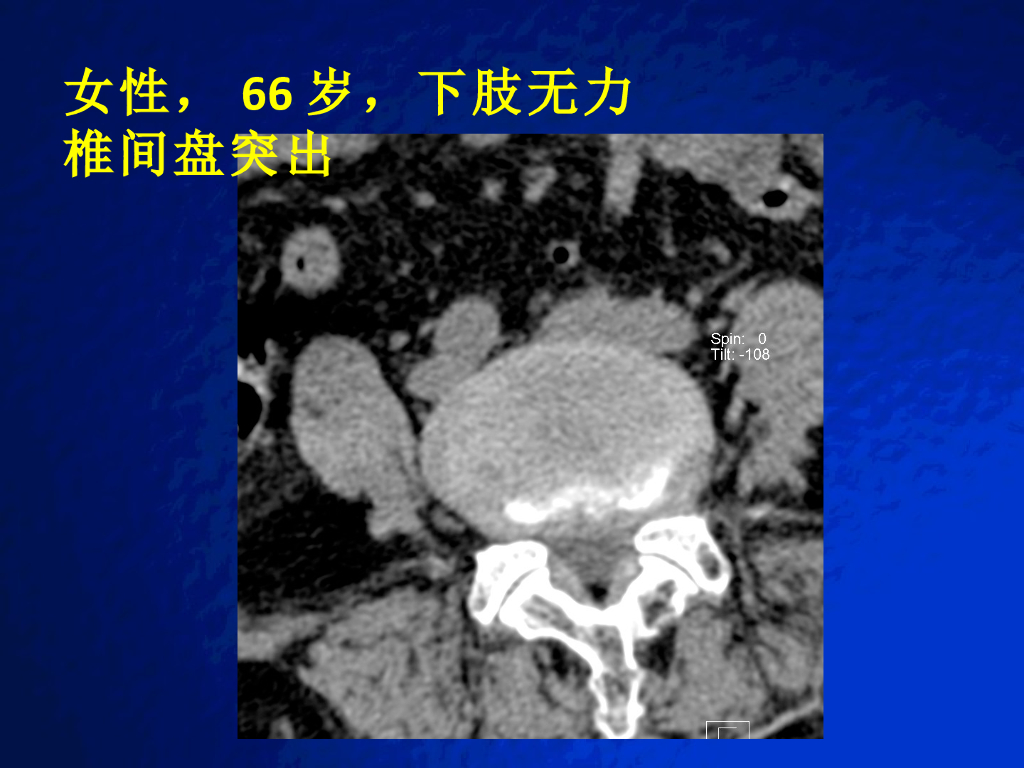

《放射诊断学》演示文稿-脊柱与软组织病变实习课.pdf